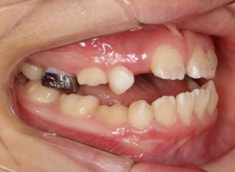

治療開始時